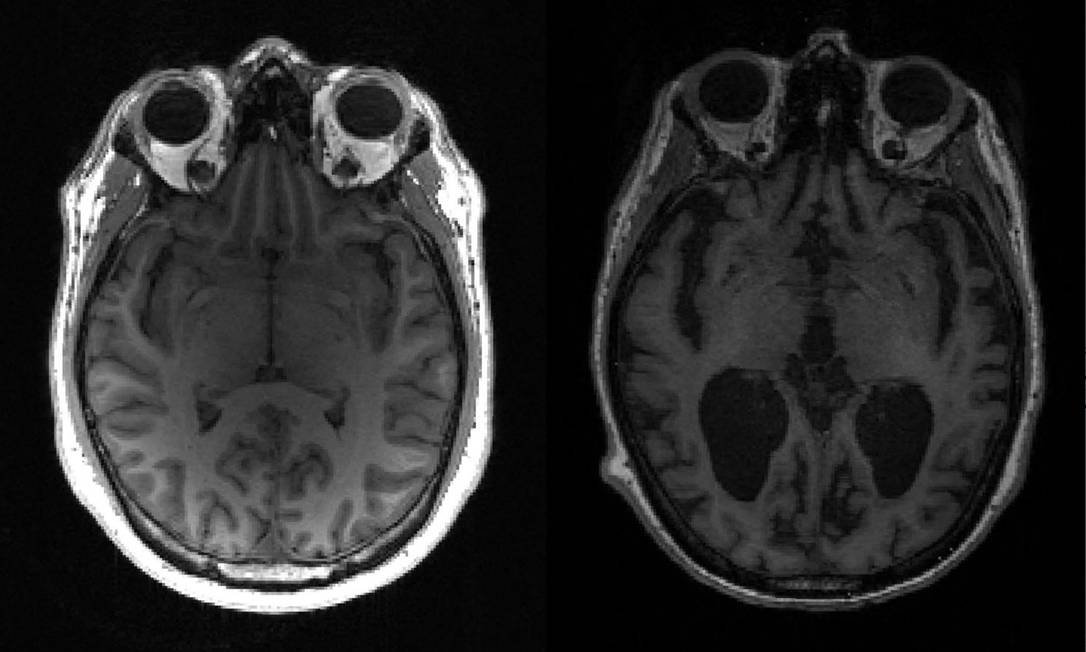

A empresa está desenvolvendo um imunizante para o Alzheimer que visa combater os oligômeros beta-amiloide — que são cadeias de proteínas que quando se acumulam no cérebro provocam as manifestações clínicas da doença. O imunizante estimula a produção de anticorpos que podem reconhecer as formas beta-amiloide capazes de desenvolver neurotoxinas.